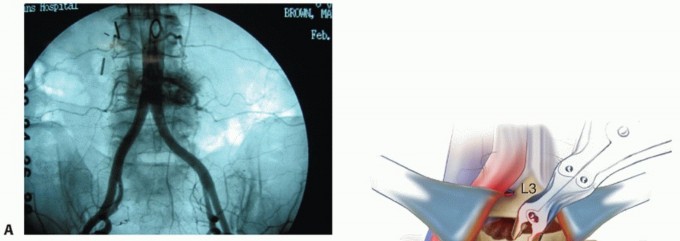

In cases of corpectomy for vascular tumors, preoperative embolization should be performed (TECH FIG 6A).

- TECH FIG 6 • A. Preembolization angiogram depicting the aortic bifurcation in a 65-year-old patient with metastatic renal cell carcinoma to the L4 vertebra. Note the degree of vascularity of the L4 vertebral body.

- B. Postembolization angiogram depicting a striking reduction in contrast entering the L4 vertebral body. Small embolization coils are seen in the vascular network surrounding the vertebral body. C. Anterior discectomy enables the surgeon to use a large rongeur to gain access to the edge of the vertebra and thereby remove the vertebral body bone.